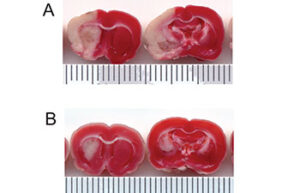

- Mice and rat brain TTC test